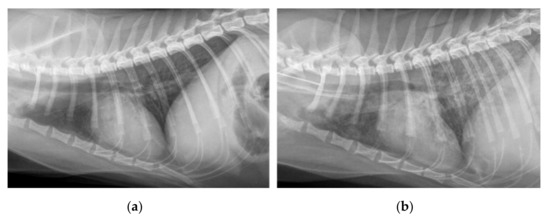

2.5. Radiography

4.6.3. Radiography

4.6.4. Image Assessment